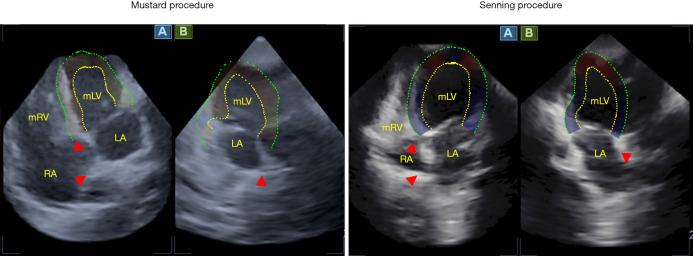

Background: Dextro-transposition of the great arteries (dTGA) stands out as a prevalent cyanotic congenital heart defect (CHD), characterized by an intricate reversal in the arrangement of the major arteries. In the past, several surgical procedures have been used to treat dTGA, including the atrial switch. Although the method is no longer used, survivors of the procedure still living among us. Recent advancements in cardiovascular imaging have led to the emergence of several novel echocardiographic techniques, notably three-dimensional (3D) and/or speckle-tracking echocardiography (STE). The present study aimed to employ 3DSTE to determine morphologic left ventricle (mLV) strain parameters in adults with dTGA who underwent Senning or Mustard procedure at infancy. Furthermore, it was also aimed to assess whether the type of correction procedure had any impact on mLV deformation parameters.

Methods: Eleven dTGA patients, with a mean age of 28.8±8.5 years (6 males, 6 Senning- and 5 Mustard-operated patients) were enrolled. They were compared to 34 healthy controls matched for age and gender (age: 35.7±12.8 years, 21 males). All subjects underwent complete two-dimensional (2D) Doppler echocardiography with 3DSTE data acquisition as per recent guidelines.